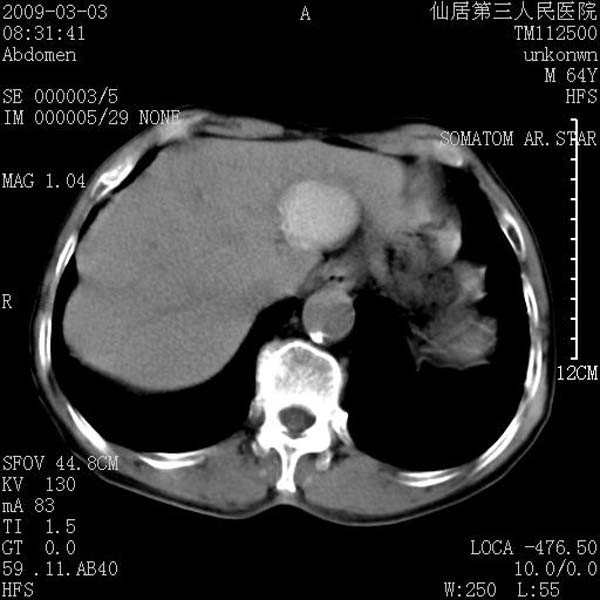

标题: CT18469:男性,64y,体检B超示肝脏低回声肿块,有胃溃疡手术 [打印本页]

患者,男性,64y,体检b超示肝脏低回声肿块,有胃溃疡手术史。

考虑----胃肠道间质瘤可能性大

从平扫及增强的特点来看,支持肝脏腺瘤并出血。

考虑胃间质瘤可能性大。

胃肠道间质瘤!

ct值呢?感觉没强化,象囊性。

考虑肝静脉韧带裂区良性占位性病变(囊肿?)。

考虑肝囊肿并出血可能性大.

考虑高密度囊肿可能性大